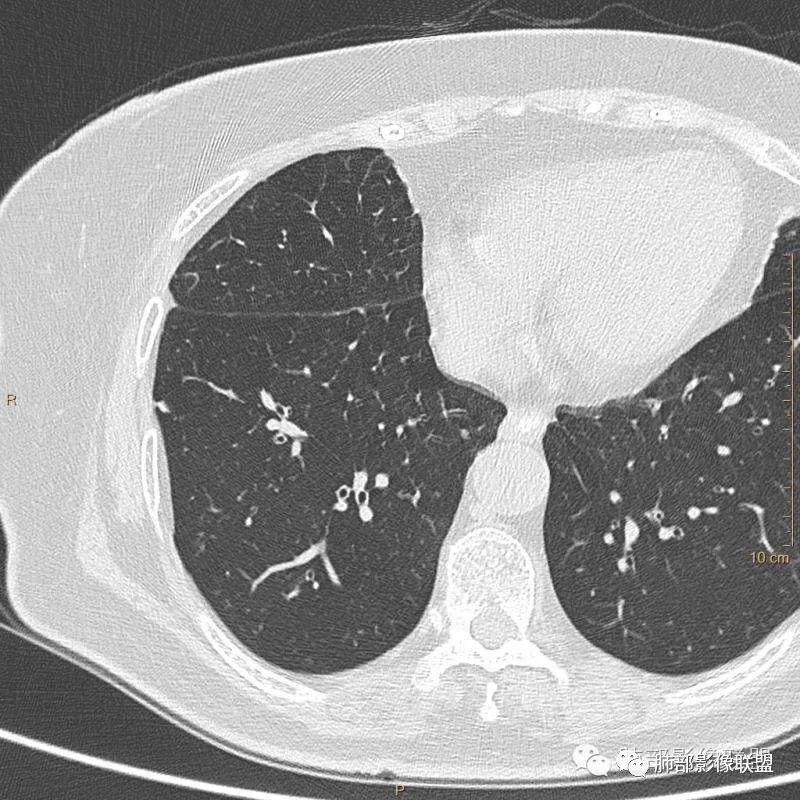

病例一:

以上病例,有什么共同点?1、病灶均位于胸膜下或叶间胸膜下;

2、病灶边缘多平直,大部分呈三角形,部分呈椭圆形;

3、病灶边缘见一条或数条细线与胸膜相连。

正常情况下,肺内淋巴结是不显示的,一般是慢性炎症所致,老年人和吸烟者多见。影像上常见于胸膜或叶间胸膜下,迄今为止,所有的报道均距胸膜或叶间胸膜小于2.0cm以内。也可以表现为与胸膜或叶间胸膜相贴的结节。绝大多数位于中下叶(气管隆突水平以下),上叶也可见到,但较少见。

长径均小于12mm。典型的形状为三角形,也可以为梭形、圆形或椭圆形。诊断的关键在于见到1-5条细线与胸膜、叶间胸膜或静脉相连,有时状如坐落于电路板的“二极管”,但以薄层CT显示为佳。有作者病理对照线状影为小叶间隔,有作者病理对照为淋巴管。其实不矛盾,因为淋巴管走行于小叶间隔内。